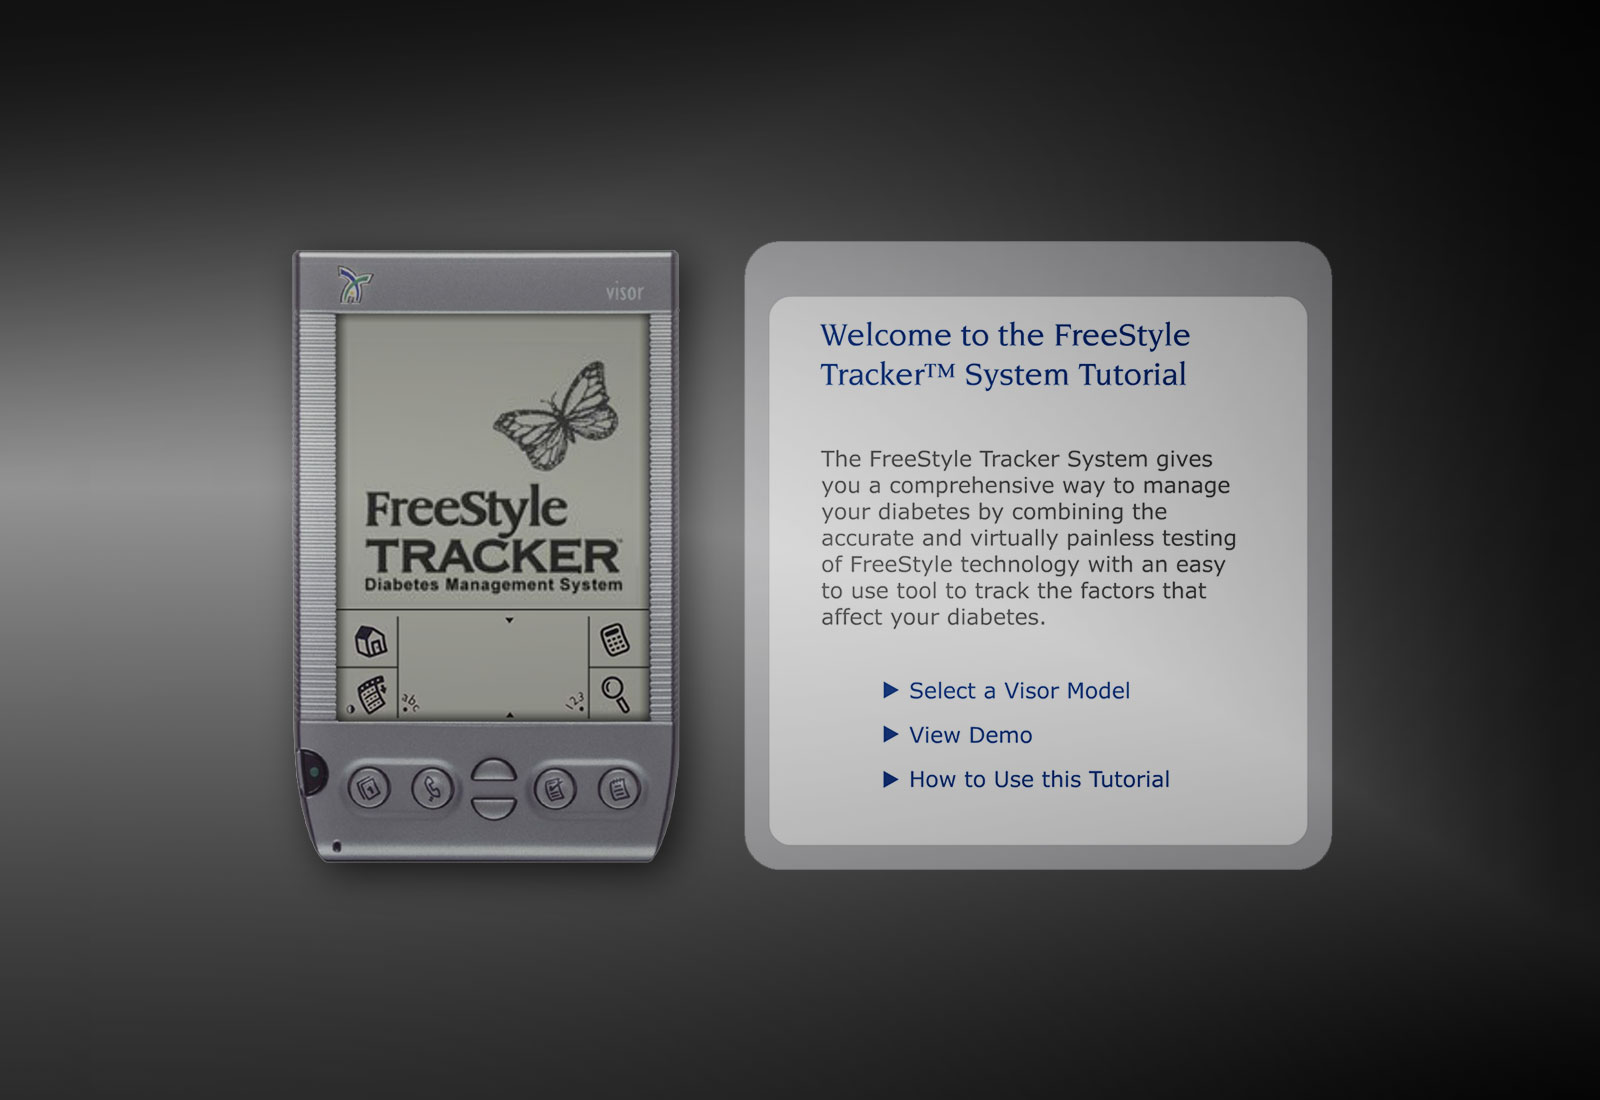

out of the blue design is a consultancy focused on solving complex global problems. For more than twenty years, we have worked with medical device, biotechnology, healthcare, and data analytics companies. Our powerful integrated brands utilize award-winning, key images to tell stories and simulate everything from the inside of a heart to the workings of a continuous diabetes monitor.